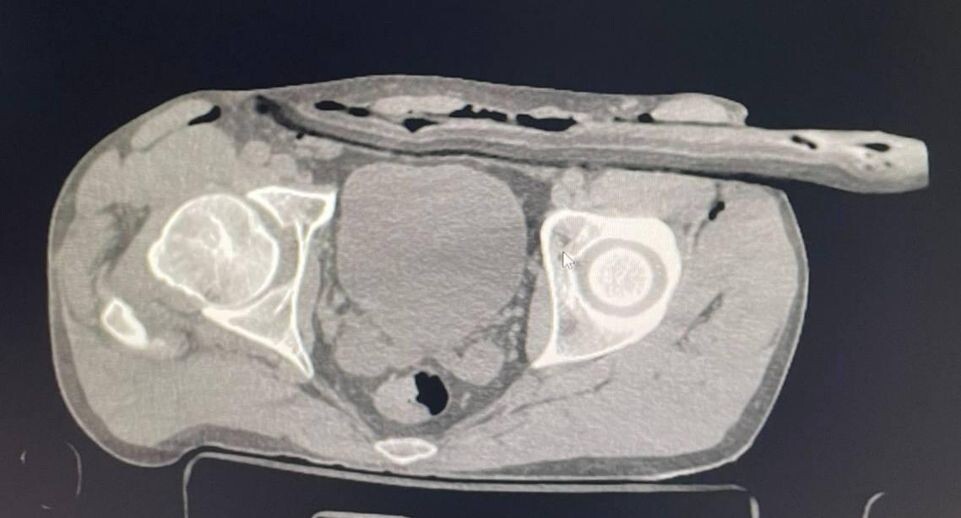

Специалисты осмотрели пострадавшего и обнаружили, что сук вошел через бедро в толщу брюшной стенки. Мужчине провели компьютерную томографию и ультразвуковое исследование, которые выявили наличие в животе свободной жидкости.

«В ходе операции мы ушили дефект в брюшине, провели ревизию органов брюшной полости, а также сделали дренаж раневого канала», — пояснил хирург Солнечногорской больницы Иван Балычев.